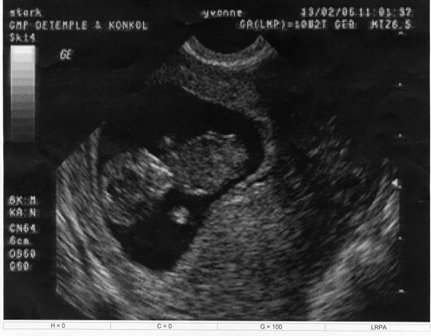

Ich war letzten Freitag zum Feinultraschall mit Nackenfaltenmessung, aber meine beiden wollten nicht.

Der Professor versuchte von oben und von unten zu schallen - nix!

Die beiden waren zumindest nicht so darstellbar, dass er ordentlich die Nackenfalte messen konnte. Aber er meinte, dass er keine gesehen hat - also alles i.O.

Und er bestätigte mir nochmal: Zwillinge - eineiig!

Übrigens brauchte ich für die Nackenfaltenmessung nichts bezahlen, weil ich als risikoschwanger gelte und beim Feinultraschall ja auch noch die Plazentaverhältnisse geklärt werden mussten (die Krümel teilen sich definitiv eine Plazenta).